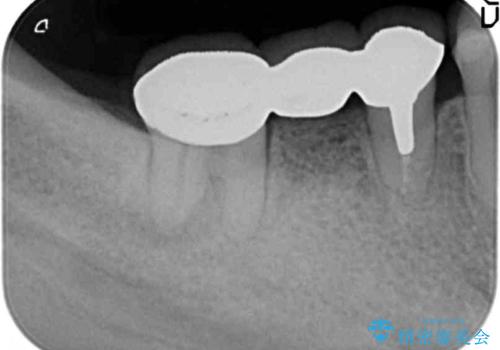

X線写真より歯の神経組織が壊死し、根尖周囲に病変を作り透過像を呈している状態でした。

咬合痛の原因となっている右下第2大臼歯の根幹治療を行ったのち、強度に優れるフルジルコニアクラウンによる咬合機能回復を計画します。